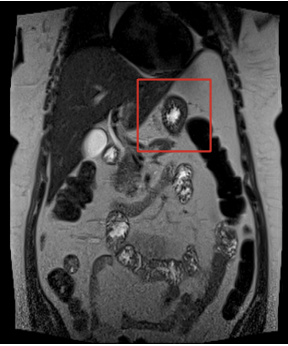

Mujer de 49 años, con antecedentes de hipertensión arterial, diabetes insípida, obesidad grado II, hipotiroidismo y trombocitosis, quien además recibió herida por proyectil de arma de fuego en abdomen a los 20 años de edad, con ruptura traumática del bazo, que requirió esplenectomía sin complicaciones. Consultó en mayo de 2022 por cuadro clínico de tres semanas de dolor abdominal, náuseas y episodios eméticos. Realizaron tomografía computarizada (TC) de abdomen, simple y contrastada, y resonancia magnética nuclear (RMN), en la que se identificó una masa con densidad de partes blandas localizada en relación con la cola del páncreas, que medía 35 x 43 x 41 mm, y que podría corresponder a una neoplasia neuroendocrina según el informe de radiología (Figura 1).

Había ausencia quirúrgica del bazo y no se reconocía dilatación del conducto pancreático.